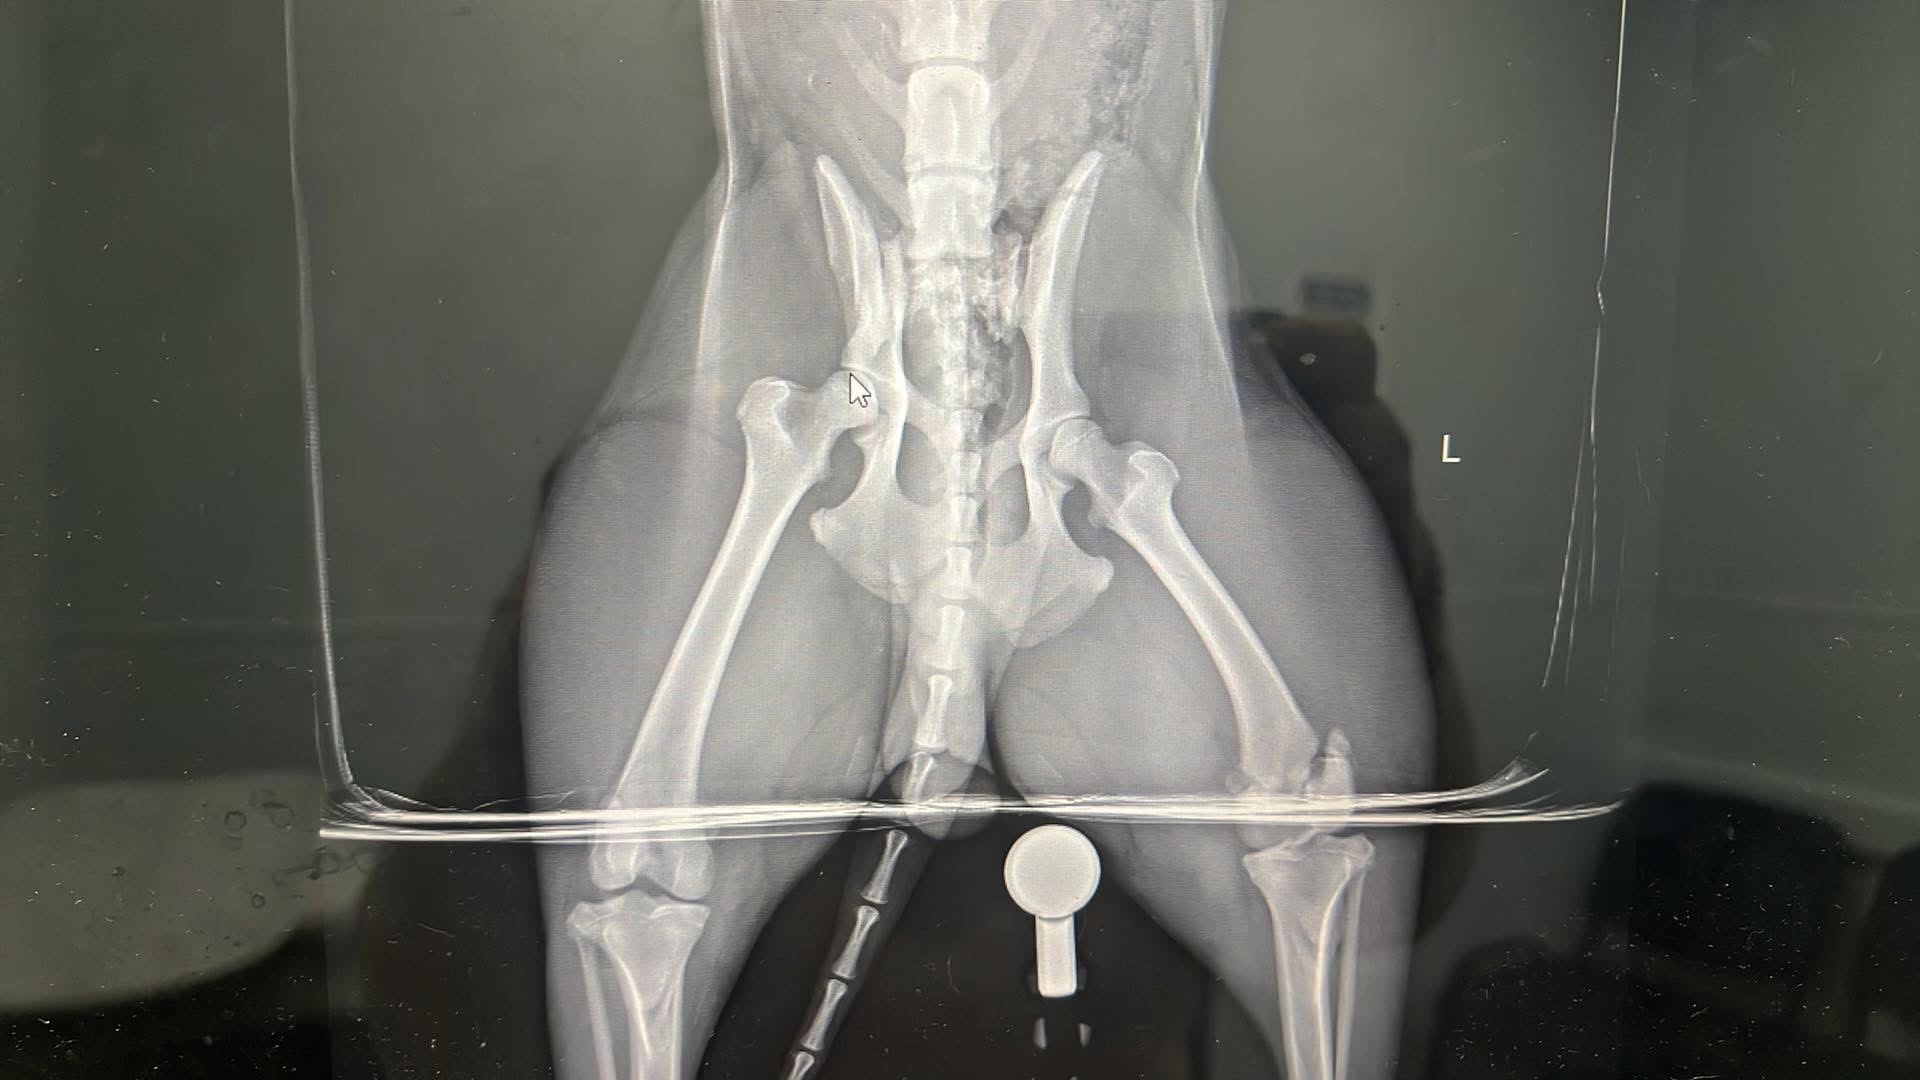

Toby has been with us since the day he was born, and he’s truly the sweetest, most gentle dog I’ve ever known. He’s a big part of our family, always bringing us joy and comfort. Recently, Toby managed to escape and was tragically hit by a car. The accident left him unable to walk, with a broken hip and two broken back legs. Watching him try his best to get up and move, despite the pain, is heartbreaking. He’s fighting so hard, and it’s clear he wants nothing more than to be back on his feet, playing and cuddling with us again.

Toby’s only chance at recovery is emergency surgery. Without it, he won’t be able to walk or enjoy the life he loves. The cost of the surgery is overwhelming for us, and we can’t imagine losing him when he’s trying so hard to stay strong. We’re reaching out to our community for help because we believe in the kindness of others and the power of coming together in tough times.

Toby’s only chance at recovery is emergency surgery. Without it, he won’t be able to walk or enjoy the life he loves. The cost of the surgery is overwhelming for us, and we can’t imagine losing him when he’s trying so hard to stay strong. We’re reaching out to our community for help because we believe in the kindness of others and the power of coming together in tough times.